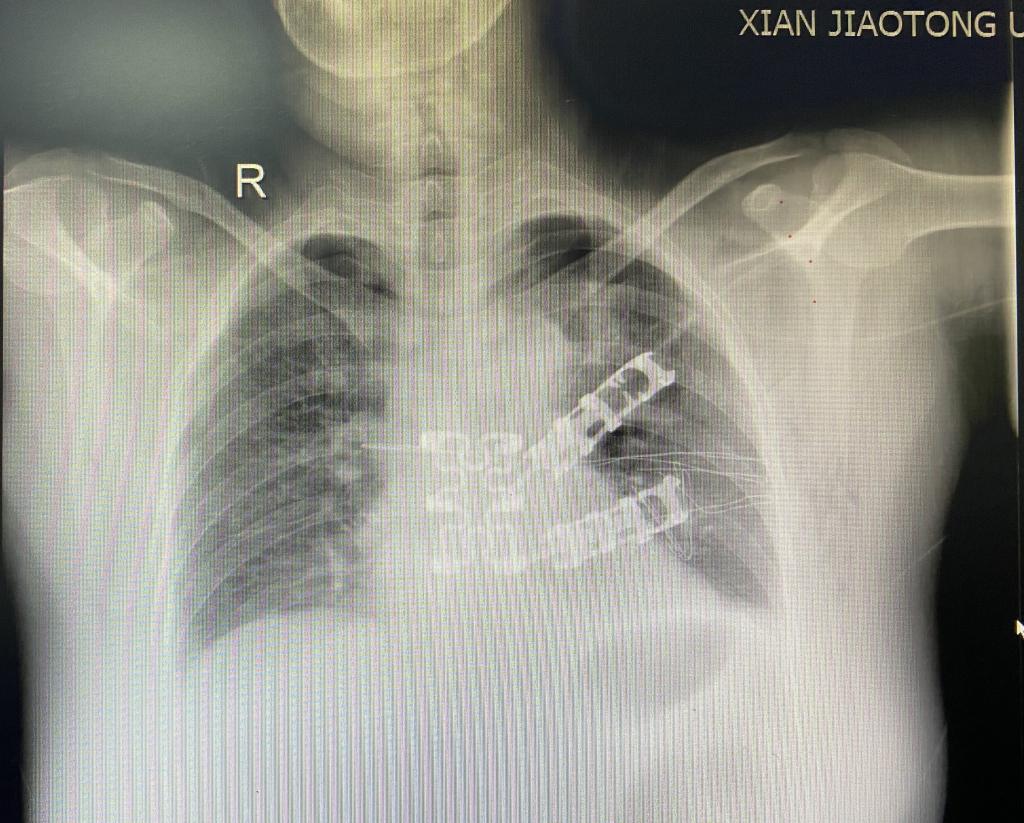

病例2:术后复查胸部X线

另一位女性患者发现左前胸壁肿物1周就诊,胸部CT示胸壁及前纵隔可见不规则软组织密度影,大小约48mmx40mm,长径约10cm,病灶与临近胸骨及左侧第2、3肋软骨分界不清。行超声引导下肿物穿刺活检,病理显示间叶来源肿瘤。肿瘤突破纵隔,侵犯了部分胸骨、左侧肋软骨以及胸部肌肉组织,此类型病例较少见,需切除部分受损胸骨及肋软骨,并对缺损的胸壁进行重建。由于缺损处较大,合适胸肋骨重建材料(如相应钢板和3D打印材料)价格昂贵,病人经济状况不能承担,李少民主任利用现有的胸骨钢板、肋骨环抱器以及经李少民主任改良的勾状的肋骨环抱器进行拼接,解决了长度的问题,稳定性上也表现出色,完美地重建了胸廓的完整性。手术入路也开创性的选择了胸腔镜和传统开胸手术结合的方式,从剑突下进行微创手术游离肿瘤的两侧及基底部,再从左侧胸壁开口,完整切除胸壁受侵组织,然后像打开“盖子”一样,移除肿瘤,避免了正中劈开胸骨的巨大创伤。手术过程顺利,术后恢复良好。